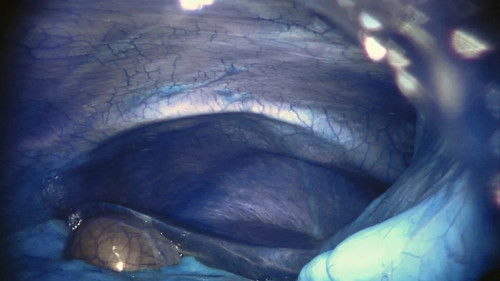

In an operating theatre in a hospital robotic surgery department, a journey through the human body is undertaken by a specialized robot named Da Vinci. The surgeon conducts the entire operation remotely, controlling the robot’s intricate movements with a joystick.